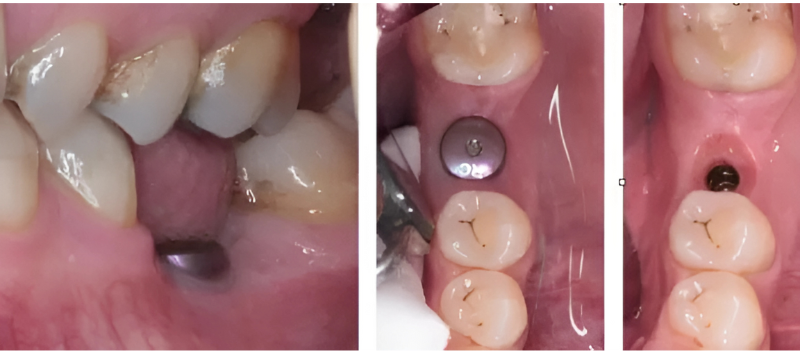

Trụ lành thương là bộ phận được đặt lên chân răng Implant sau quá trình đặt trụ Implant